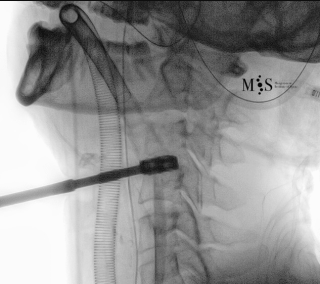

Images showing the endoscopic placement of a cage into a cervical disk

Animated image showing the endoscopic insertion of an intervertebral cage into a cervical disk.

Note the distraction of the disk space during as the cage is inserted.